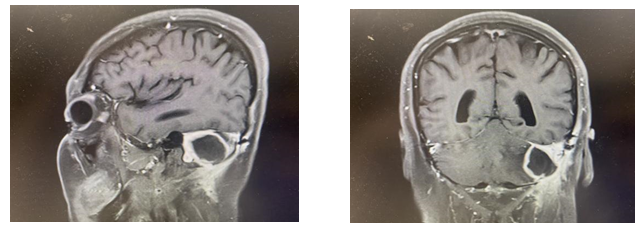

图:核磁提示脑脓肿形成

术后1个月(2024-2-27)患者无明显诱因出现头晕,有四肢感觉麻木,患者于天坛医院复诊,行核磁检查,考虑脑脓肿。急诊予以万古霉素+美罗培南+地塞米松+甘露醇治疗1天后状态明显好转。